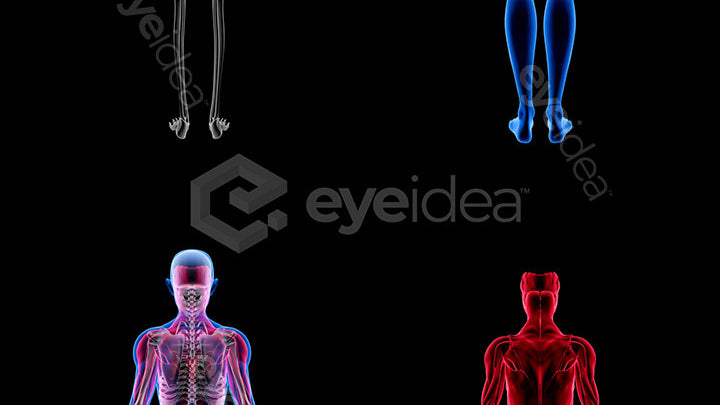

Versatility and Variety

Our Stock-Packs™ are curated to include a varied

range of angles, motion, styles and formats,

ensuring that creators can find the assets

they want fast and easy.